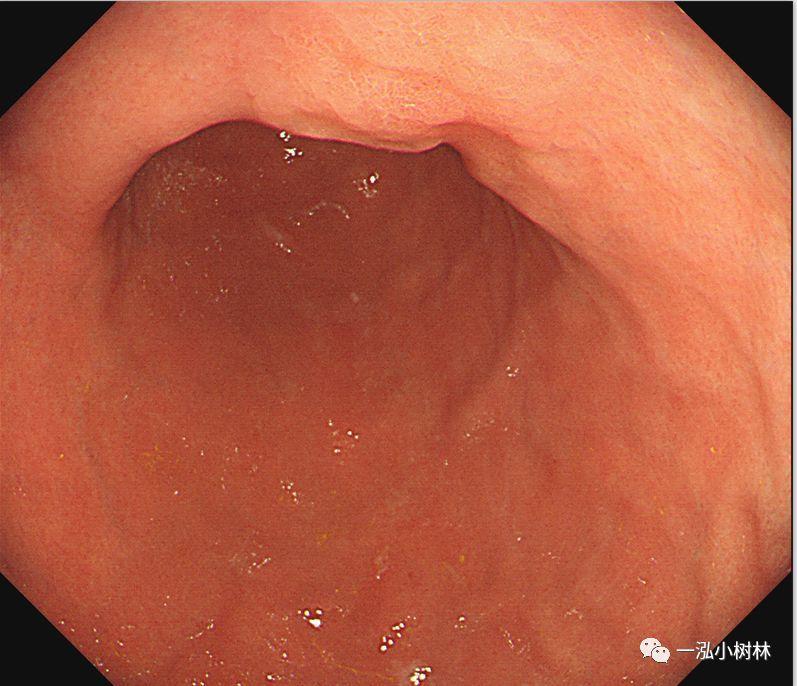

例4 胃体下部病变

图4b 白光内镜:胃体下部高分化腺癌(Tub1)